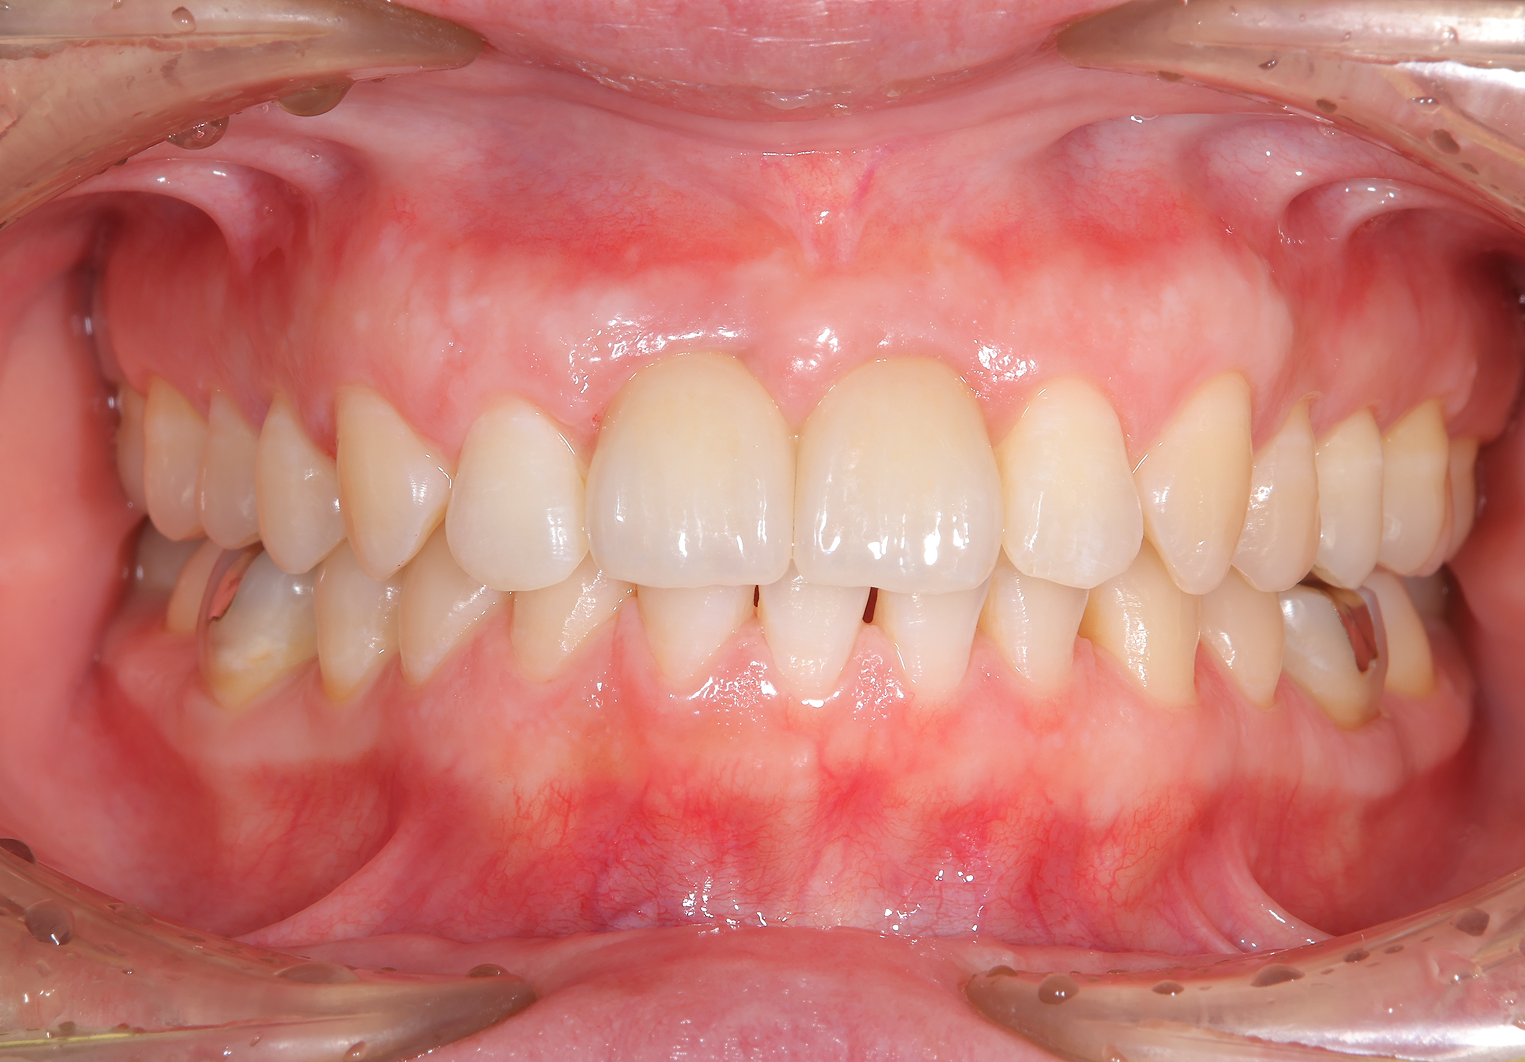

治療概要:左上(写真では右)の真ん中の歯、根元の方にニキビのようなできものができています。診査の結果この歯は根が割れており、抜歯と判断しました。

治療前

治療後

前歯2本がインプラント治療に至った背景

お口全体を検査したところ、自覚はありませんでしたが、右の前歯もレントゲンを見ると歯の根の中腹あたりが溶けてしまっています。この歯も残念ながら抜歯となると判断しました。